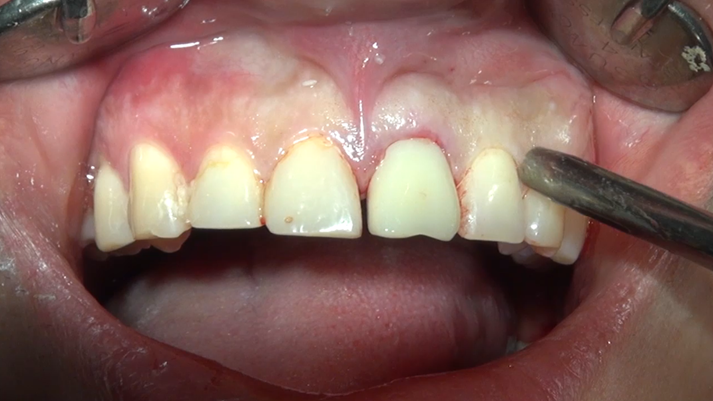

Clinical case: Extraction, immediate placement & loading using

R2GATE solution in aesthetic zone

- Courtesy of Dr. Jong-Cheol Kim, Korea-

Dr. Jong Cheol Kim, immediate loading, digital guided surgery, Digital ONE-DAY Implant, maxillary anterior, #21, guided surgery, immediate loading, AnyRidge, R2GATE, Mega ISQ, MEG Torq, R2GATE Full Surgical Kit

AnyRidge implant system, R2 Guide, R2GATE Full Surgical Kit, Mega ISQ